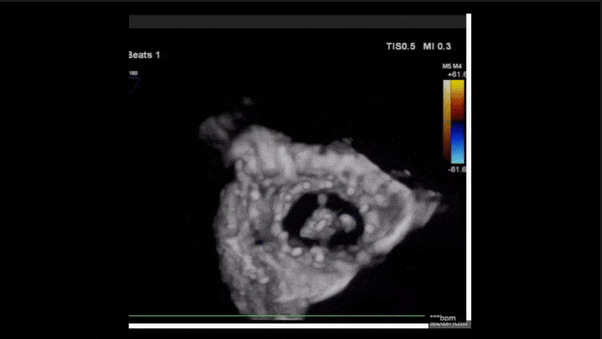

術(shù)前TEE評估

1、3D TEE顯示雙房及右室擴(kuò)大,右室中段直徑40mm,右室FCA 52%。三尖瓣環(huán)TAPSE 22mm,三尖瓣環(huán)左右徑49mm,三尖瓣隔葉長度16mm,前葉長度21mm,后葉長度34mm,三尖瓣前隔gap 11mm,后隔gap 5.6mm,AP gap 12mm,診斷極重度功能性三尖瓣返流(Type I型三尖瓣:Torrential FTR 5+)。

術(shù)后即刻返流三維

術(shù)后三維超聲